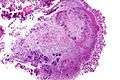

-

Micrograph of actinomycosis, H&E stain